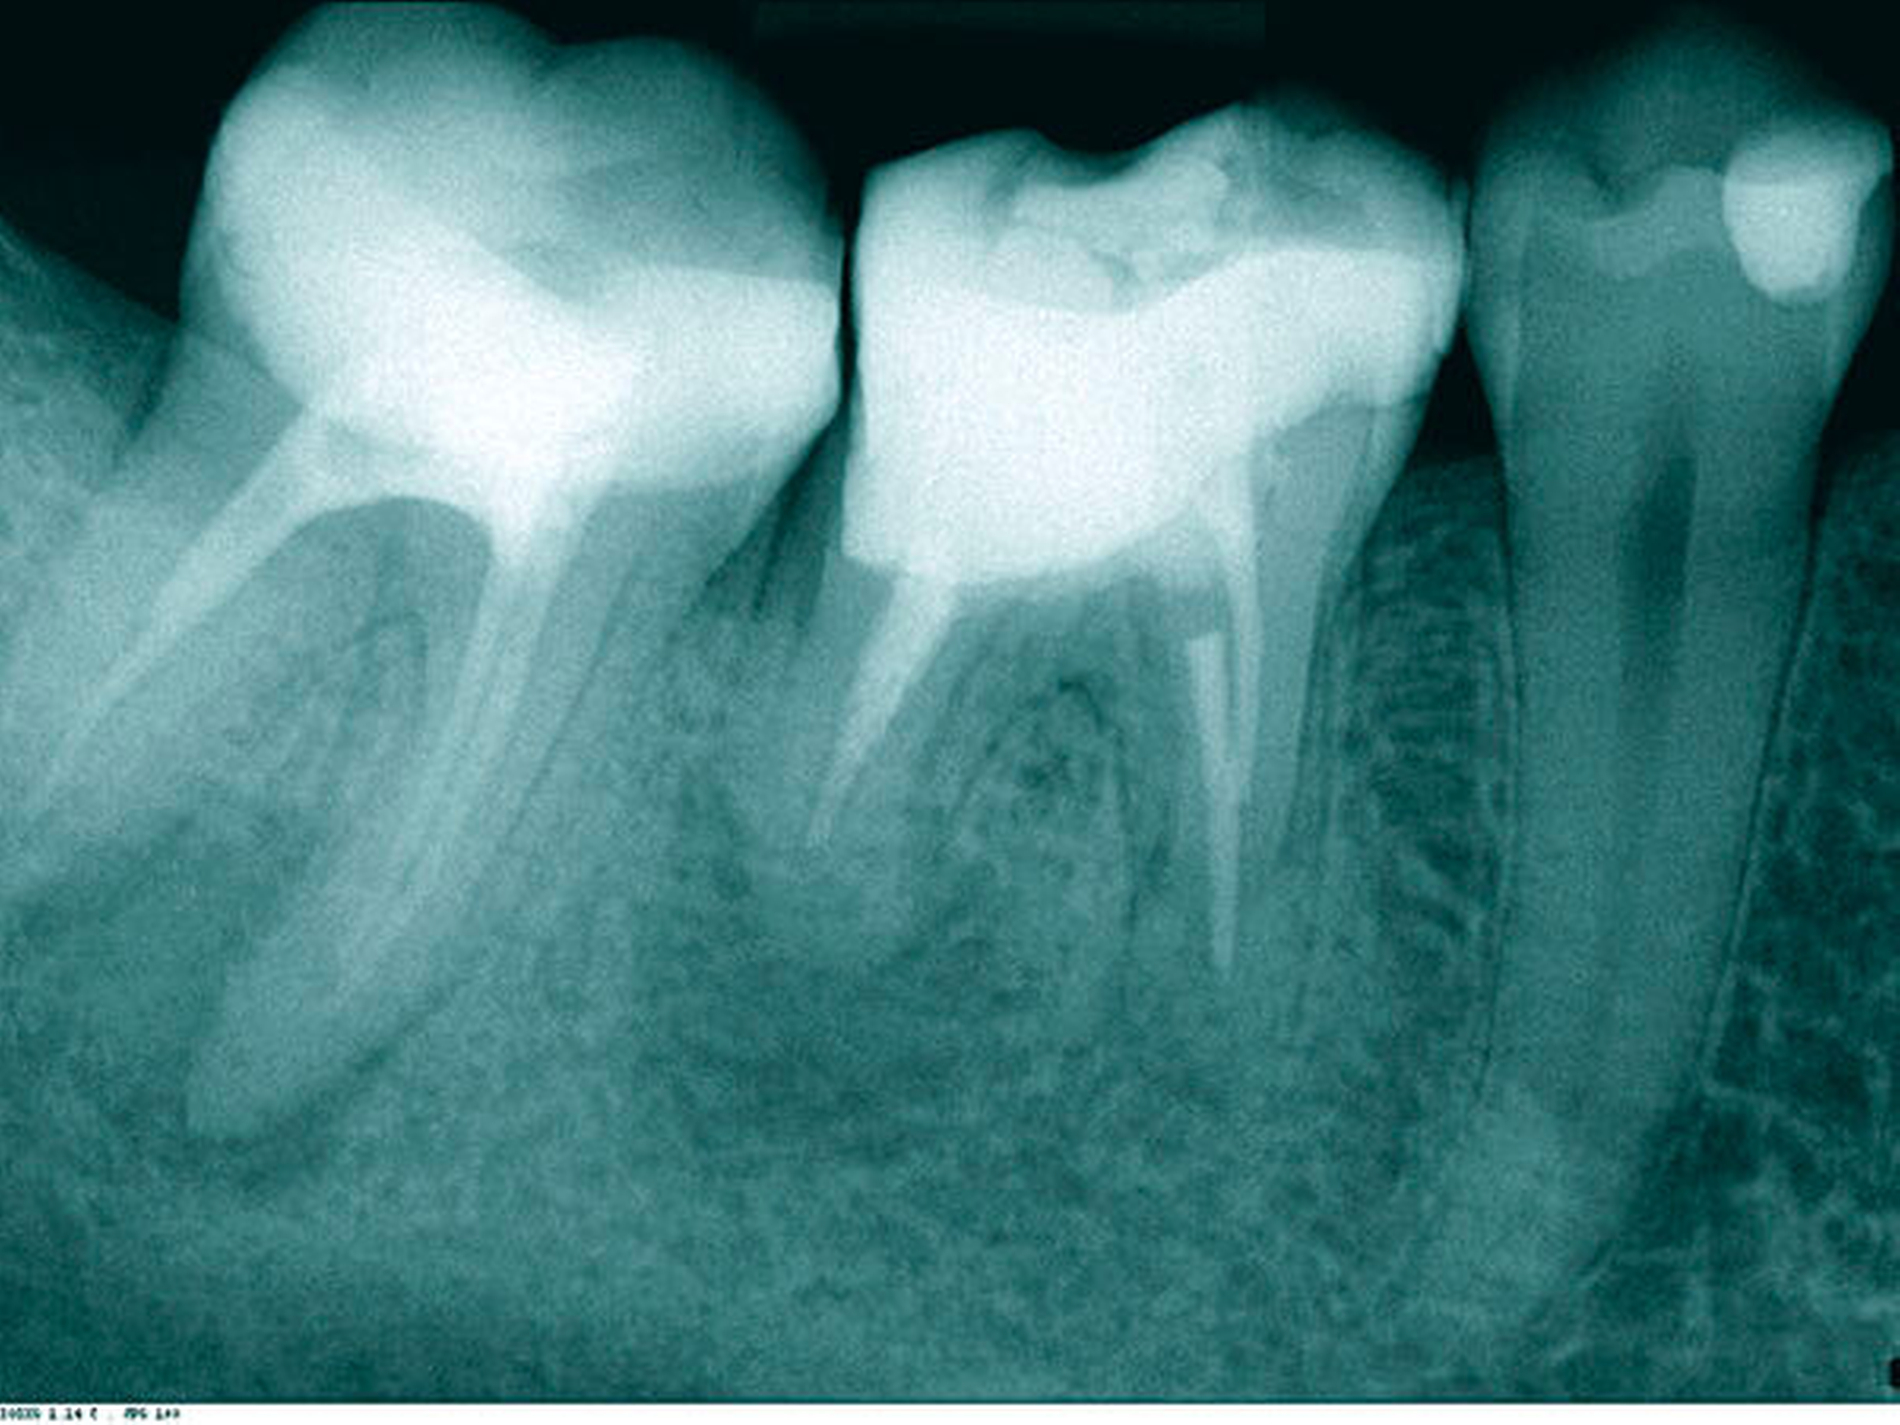

In der ersten Therapiesitzung erfolgte – nach Isolierung mit Kofferdam – die Trepanation des Zahnes und die Stiftentfernung mit Ultraschallinstrumenten. Im Anschluss wurden die drei gefüllten Kanäle revidiert, der vierte, nicht abgefüllte, mesiobukkale Kanal dargestellt und präpariert. Die elektronische Längenmessung ergab 14,5 mm für den mesiobukkalen Kanal, 17,0 mm für den mesiolingualen, 15 mm für den distobukkalen und 16 mm für den distolingualen. Aufgrund der großen initialen Kanaldurchmesser und der guten Einsicht bis ins periapikale Gewebe (Abbildung 2) wurde auf eine Längenmessaufnahme verzichtet. Die Desinfektion erfolgte mit Natriumhypochlorid (NaOCl) 5 Prozent und EDTA 17 Prozent, sowie Schallaktivierung mittels EDDY-Spitzen (VDW, München). Das Wurzelkanalsystems wurde manuell mit K-Feilen bis IS0 70 präpariert. Es folgte eine medikamentöse Einlage mit AH Temp (DentsplySirona, Bensheim). Danach wurde eine Aufnahme zur Kontrolle der vollständigen Guttapercha-Entfernung und der suffizienten Einbringtiefe des Kalziumhydroxids angefertigt (Abbildung 3).

Bereits nach der ersten Sitzung war der Patient symptomfrei. In der zweiten Sitzung wurden nach erneuter ausgiebiger Reinigung und Desinfektion des Kanalsystems in allen vier Wurzelkanälen apikale Plugs mit Total Fill BC Root Repair Material (FKG, La Chaux-de-Fonds, Schweiz) appliziert (Abbildungen 4 und 5) und es wurde eine Röntgenaufnahme zur Kontrolle der Plugs angefertigt (Abbildung 6). Anschließend wurden die restlichen Kanalanteile mit Total Fill BC Sealer und warmer-vertikaler Fülltechnik abgefüllt, der Zahn wurde adhäsiv verschlossen und ein Röntgenkontrollbild angefertigt (Abbildung 7). Bei der Verlaufskontrolle nach sechs Monaten war radiologisch bereits ein deutlicher Rückgang der Läsion zu erkennen (Abbildung 8), der Patient war nach wie vor symptomfrei.